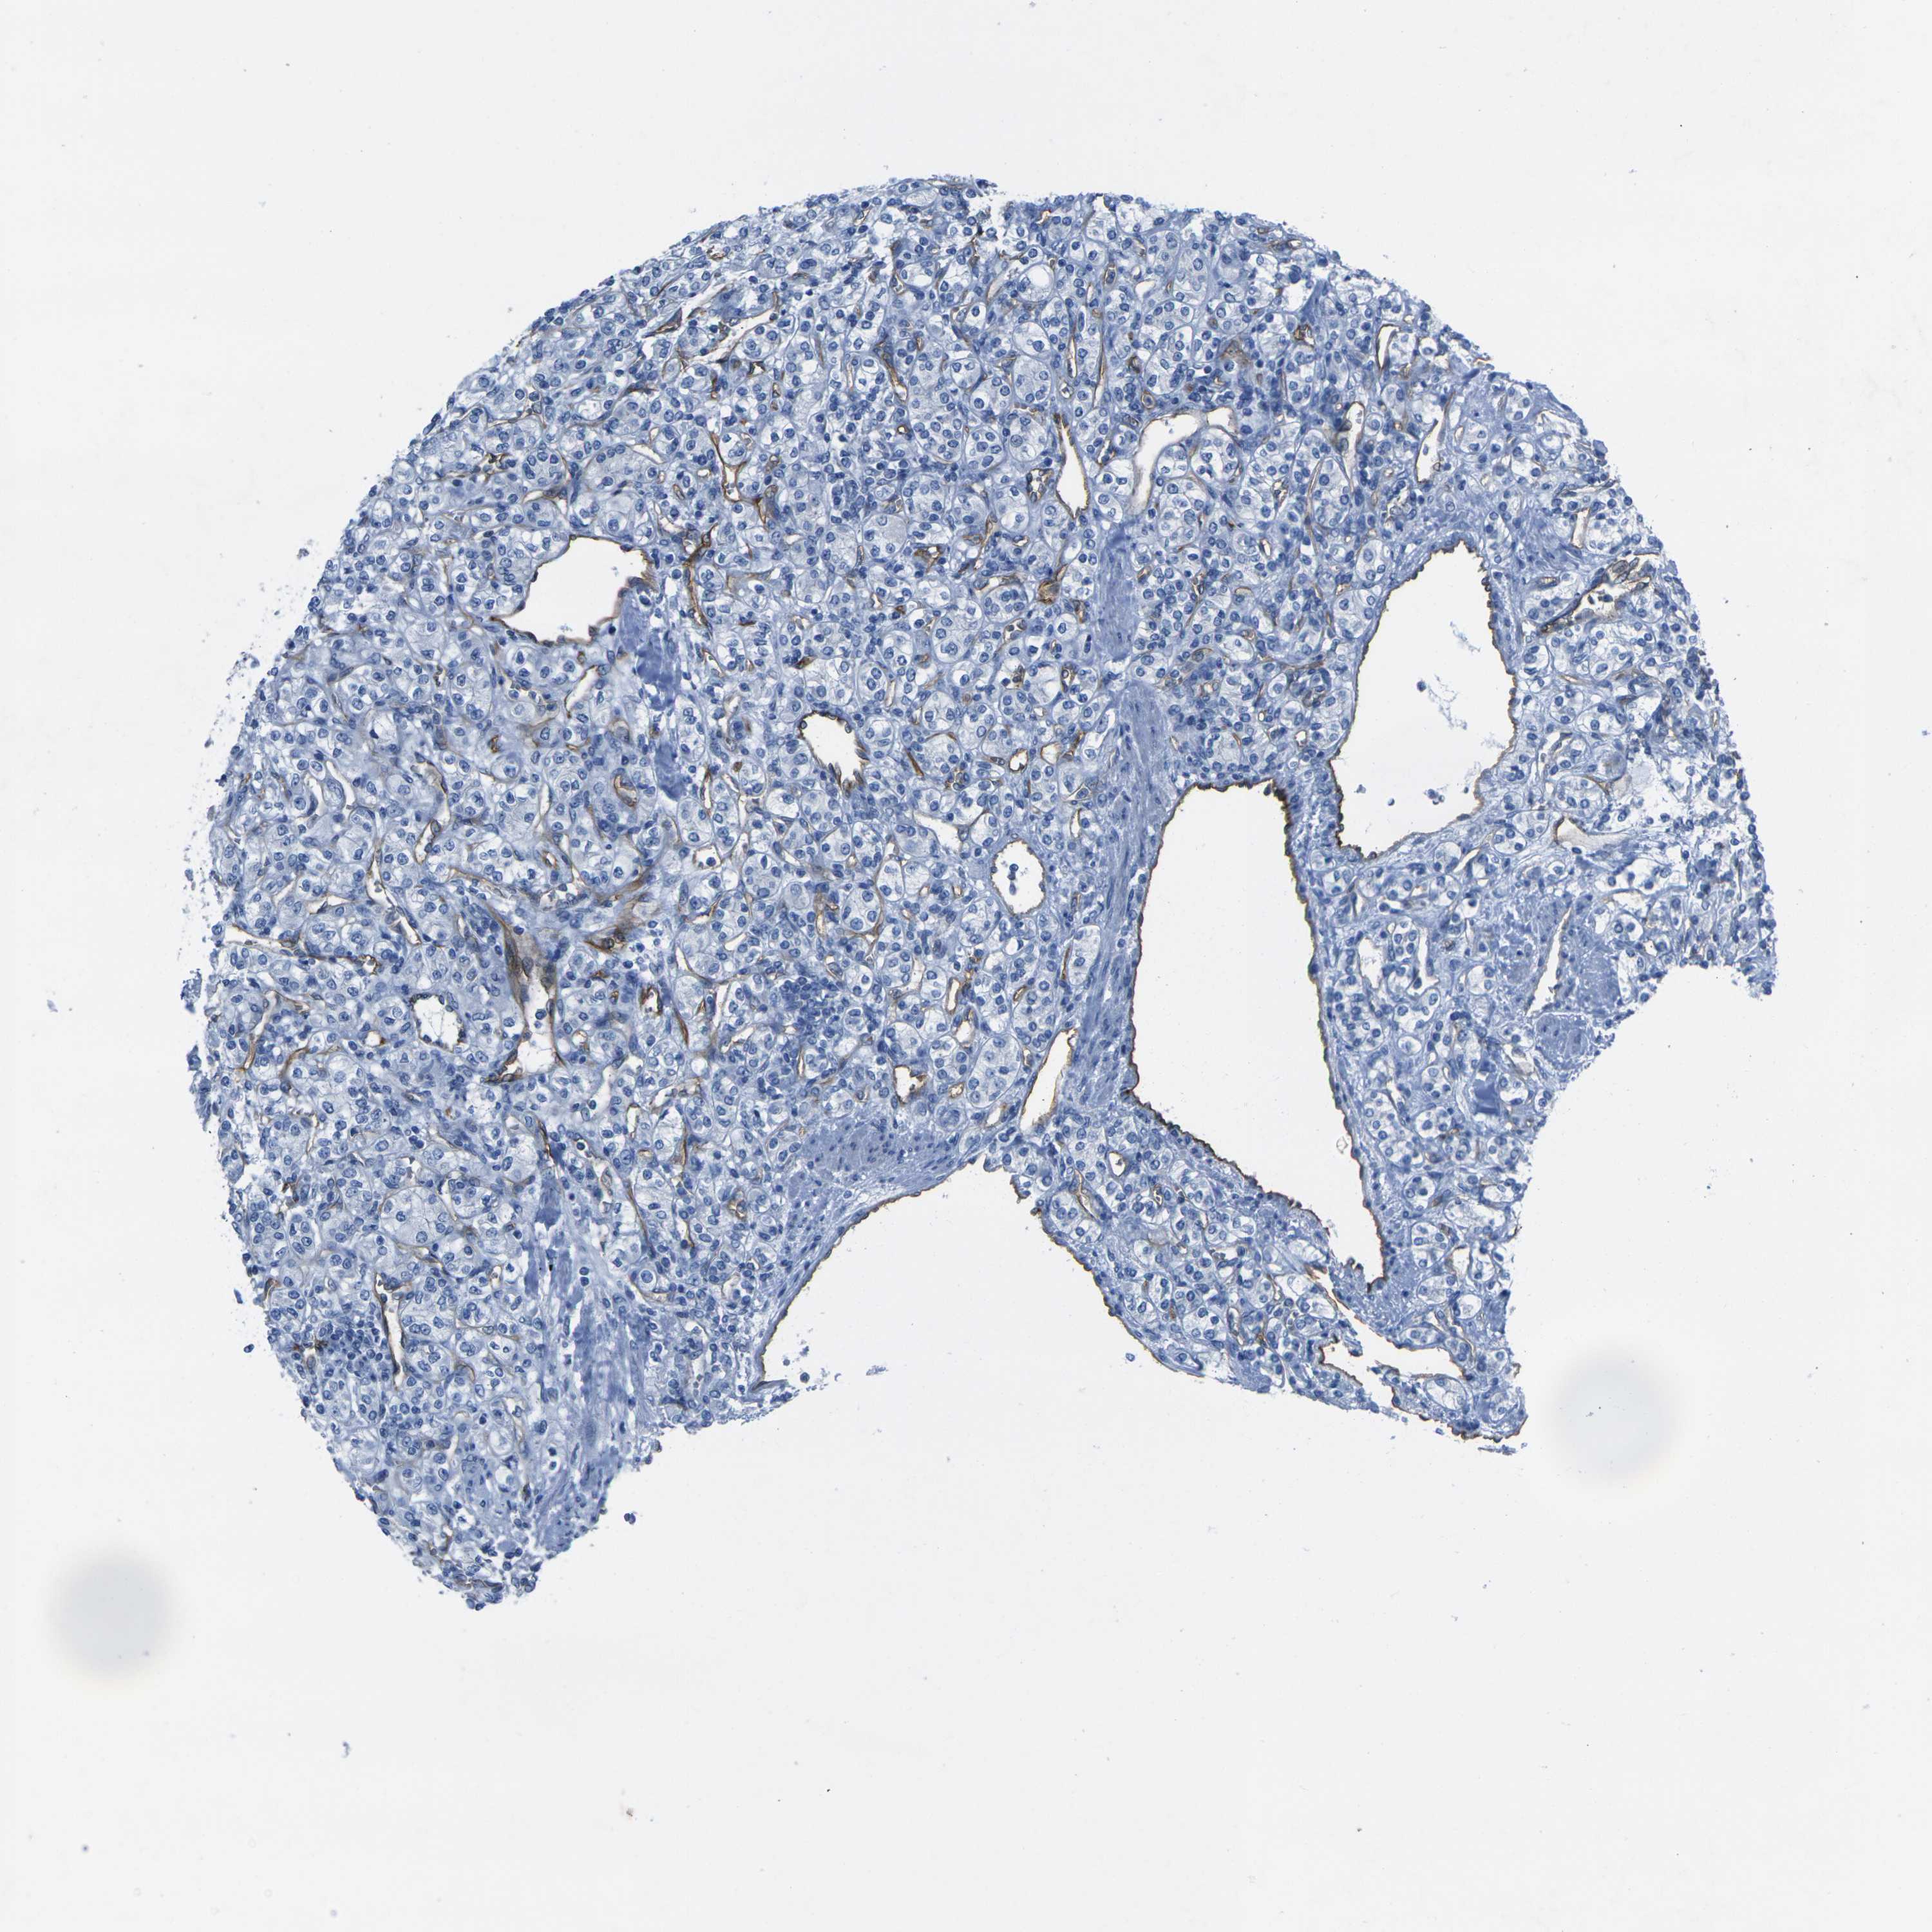

KIDNEY RENAL CLEAR CELL CARCINOMA (TCGA) - Interactive survival scatter ploti

The Survival Scatter plot shows the clinical status (i.e. dead or alive) for all individuals in the patient cohort, based on the same data that underlies the corresponding Kaplan-Meier plots. Patients that are alive at last time for follow-up are shown in blue and patients who have died during the study are shown in red.

The x-axis shows the expression levels (FPKM) of the investigated gene in the tumor tissue at the time of diagnosis. The y-axis shows the follow-up time after diagnosis (years). Both axes are complimented with kernel density curves demonstrating the data density over the axes. The top density plot shows the expression levels (FPKM) distribution among dead (red) and alive patients (blue). The right density plot shows the data density of the survived years of dead patients with high and low expression levels respectively, stratified using the cutoff indicated by the vertical dashed line through the Survival Scatter plot. This cutoff is automatically defined based on the FPKM cutoff that minimizes the p-score. The cutoff can be changed by dragging the vertical line or by entering a cutoff value in the square labeled "Current cut-off".

Under the Survival Scatter plot the p-score landscape (black curve; left axis) is shown together with dead median separation (red curve; right axis). Dead median separation is the difference in median mRNA expression between patients who have died with high and low expression, respectively. It is calculated as follows: median FPKM expression of dead patients with high expression - median FPKM expression of dead patients with low expression. This is intended to aid the user in visually exploring custom cutoffs and the associated p-scores and dead median separation.

Individual patient data is displayed and can be filtered by clicking on one or more of the category buttons on the top of the page. Categories describing expression level and patient information include: high, low, alive, dead, female, male and tumor stages. The scale of the x-axis can be toggled between linear and log-scale by clicking on the "x log" button. Mouse-over function shows TCGA ID, patient information and mRNA expression (FPKM) for each patient.

& Survival analysisi

Kaplan-Meier plots summarize results from analysis of correlation between mRNA expression level and patient survival. Patients were divided based on level of expression into one of the two groups "low" (under cut off) or "high" (over cut off). X-axis shows time for survival (years) and y-axis shows the probability of survival, where 1.0 corresponds to 100 percent.

HSPA12B is validated prognostic, high expression is favorable in Kidney Renal Clear Cell Carcinoma (TCGA)

: 3.4

Average pTPM 7.5

Number of samples 521